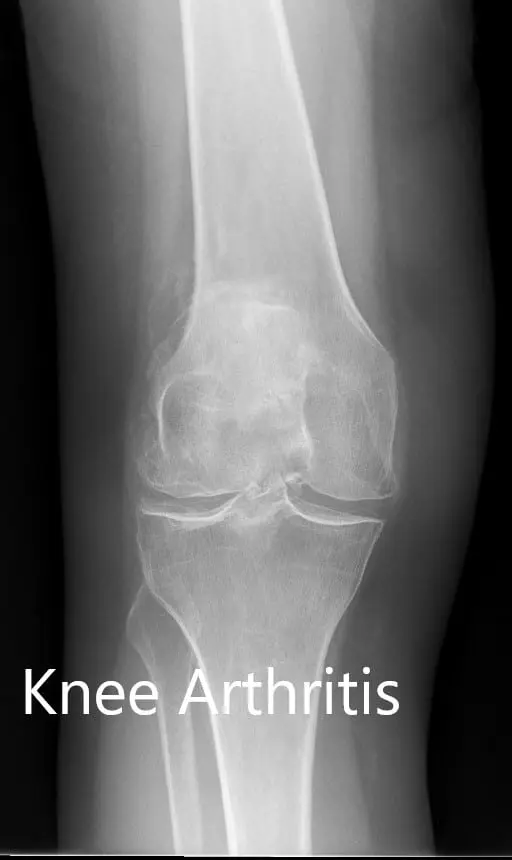

Preoperative X-ray showing the AP view of the left and the right knee respectively

Preoperative X-ray showing the AP view of the left and the right knee respectively - img 2